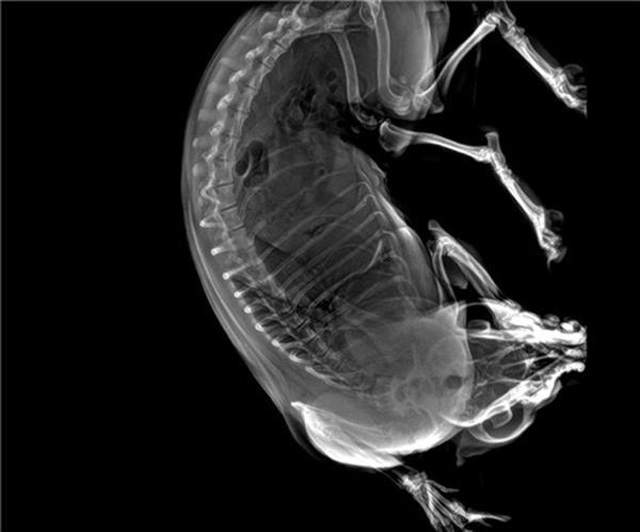

寵物DR的工作原理是X光線穿透動物體后在屏幕或者膠片上面顯示體內(nèi)影像。輔助寵物醫(yī)生讀片跟準(zhǔn)確的治療,寵物DR顯示是寵物醫(yī)院診所的配置,提高了診斷的效率。DR的檢測效率比X線高44%,成像快采集時間10MS以下。3秒左右就可以看到檢查圖像。常規(guī)的胸部DR還要幾分鐘。所以寵物DR的出片速度是非??斓?。很高的空間分辨率低噪音。可以獲得高清圖像,提高檢測正確率避免誤診等等問題。數(shù)字化圖像的優(yōu)勢是可以保留原始數(shù)據(jù),圖片識別,二三維的重建,醫(yī)學(xué)影像學(xué)實現(xiàn)全數(shù)字化和無膠片化鋪平了道路。提供照片打印服務(wù),防止照片丟失而重復(fù)照片。有針對性的對圖像進行處理,以提高診斷率。寵物DR的輻射量很低的,對人體的輻射風(fēng)險不大。